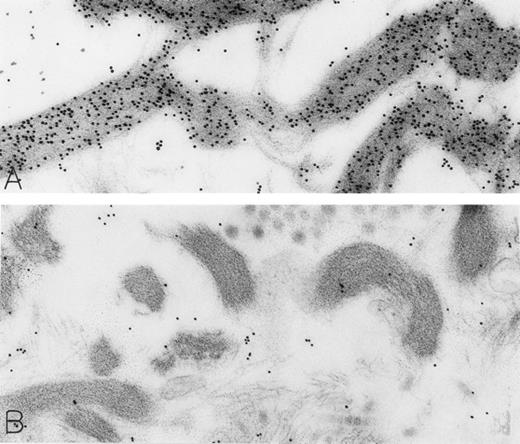

Mast cell granules in skin biopsies of rhSCF-injected sites from patients who had received rhSCF for 6 days (A and B; obtained 2.5 hours after the SC injection of 5 μg/kg of rhSCF in patient no. 2) or 13 days (C and D, obtained 2 hours after the SC injection of 5 μg/kg of rhSCF in patient no. 1). The photomicrographs illustrate the ultrastructure of electron-dense granules in nonsecretory mast cells. Parallel crystalline arrays, oriented either in several directions (A) or all in one direction (C), are typical for the cytoplasmic granules of human skin mast cells. The DAO-gold staining (A) was largely abrogated by absorption of the DAO-gold with solid-phase histamine before staining (C). The granule in (B) is filled with a membranous scroll pattern that is also heavily labeled with the DAO-gold. The DAO-gold staining is not seen in the scroll granule in (D) from a section that was digested on the grid with DAO before DAO-gold staining. Original magnifications: (A) ×110,000; (B) ×136,500; (C) ×93,000; and (D) ×72,000.

As noted in our previous reports,6 14 ultrastructural evidence of anaphylactic-type degranulation, including the extracellular extrusion of membrane-free cytoplasmic granules, was observed only in biopsies from sites that had been directly injected with rhSCF. Using the DAO-gold enzyme-affinity method, reactivity (gold label) was very strong in the granules of nonsecretory mast cells (in biopsies of either control or rhSCF-injected sites) as well as in any electron-dense cytoplasmic granules remaining in the cytoplasm of skin mast cells that were undergoing secretion (Figs 1, 2, and 3). Moreover, retention of DAO-gold labeling (indicating the presence of histamine) was evident in cytoplasmic granules that exhibited all of the substructural patterns that can be observed in human skin mast cells (Fig 3). Such patterns include granules with crystal (Fig 3A), scroll (Fig 3B), or mixed patterns.

Specificity controls for the histaminase-gold-based affinity technique, including absorption of the DAO-gold reagent by solid-phase histamine before sample staining (Figs 2C and 3C) and digestion of the section with histaminase before DAO-gold staining (Figs 1B and 3D), showed a marked reduction of label or a complete absence of reactivity. In every case tested, there was no staining of sections with colloidal gold alone (data not shown).